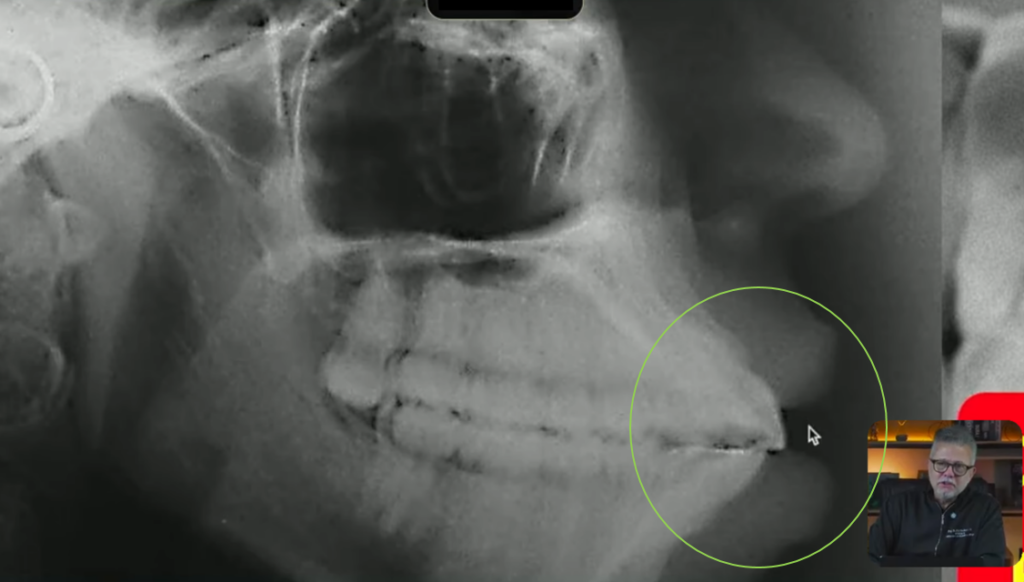

Minha paciente nesse caso não consegue nem fechar a boca direitinho aqui, vocês estão conseguindo ver isso?

Então nós estamos diante de uma paciente biprotrusa com incisivos inclinados para vestibular

E aqui eu tiro a prova dos 9, eu tenho certeza absoluta que esse incisivo está vestibularizado porque eu tracei o longo eixo dele, ele passou muito atrás dessa órbita: